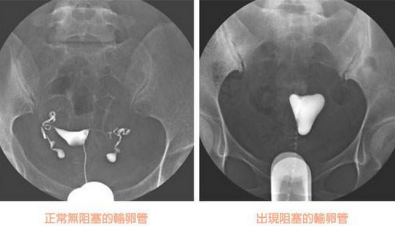

輸卵管造影檢查,精準了解輸卵管病變情況

輸卵管造影是用來檢查女性輸卵管通暢與否的一種檢測方法。目前,輸卵管造影是臨床上應用較為廣泛的方法之一。造影是通過導管經陰道、宮頸、子宮腔直接插向子宮角的輸卵管開口處,對著輸卵管推注造影劑而使輸卵管顯影,進而了解輸卵管是否通暢、阻塞部位及宮腔形態的一種檢查方法。